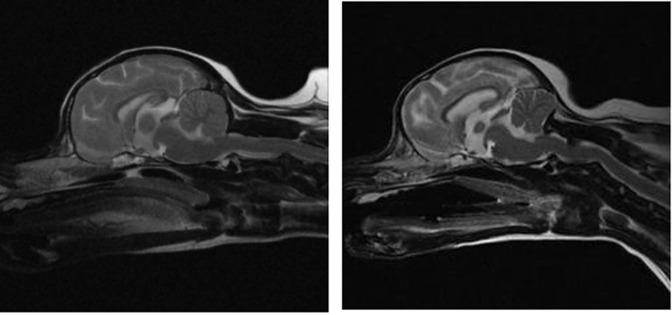

Endocranial magnetic resonance images of both normal dogs and dogs diagnosed with Chiari-like malformation were retrospectively analyzed. Measurements of the caudal cranial fossa volume, rostral and medial fossa volume, and volume index were taken. The differences in caudal cranial fossa volume and volume index between normal dogs and those diagnosed with Chiari-like malformation were then utilized to create a rat model of Chiari-like malformation through surgical intervention. The measurements were conducted on both the rat Chiari-like malformation models and normal rats, with each measurement taken twice and the mean values calculated.

Significant differences were found between normal dogs and dogs diagnosed with Chiari-like malformation in terms of the volume of the caudal cranial fossa (27.62% reduction) and the volume index (23.36% reduction) (p<0.05). These differences were used to develop a rat model, which also showed significant reductions in both caudal cranial fossa volume (29.52%) and volume index (28.30%) compared to normal rats (p<0.05). The condition in the rat model was confirmed through magnetic resonance imaging, which revealed cerebellar herniation into the foramen magnum.

回顾性分析了正常犬和诊断为 Chiari 样畸形犬的颅内磁共振图像。测量颅后窝容积、颅前窝和颅中窝容积以及容积指数。然后,利用正常犬和 Chiari 样畸形犬的颅后窝容积和容积指数的差异,通过手术干预来建立 Chiari 样畸形大鼠模型。对大鼠 Chiari 样畸形模型和正常大鼠进行测量,每个测量重复两次,计算平均值。

正常犬和 Chiari 样畸形犬在颅后窝容积(减少 27.62%)和容积指数(减少 23.36%)方面存在显著差异(p<0.05)。这些差异用于建立大鼠模型,与正常大鼠相比,大鼠模型的颅后窝容积(减少 29.52%)和容积指数(减少 28.30%)也显著降低(p<0.05)。磁共振成像证实了大鼠模型的小脑疝出到枕骨大孔。